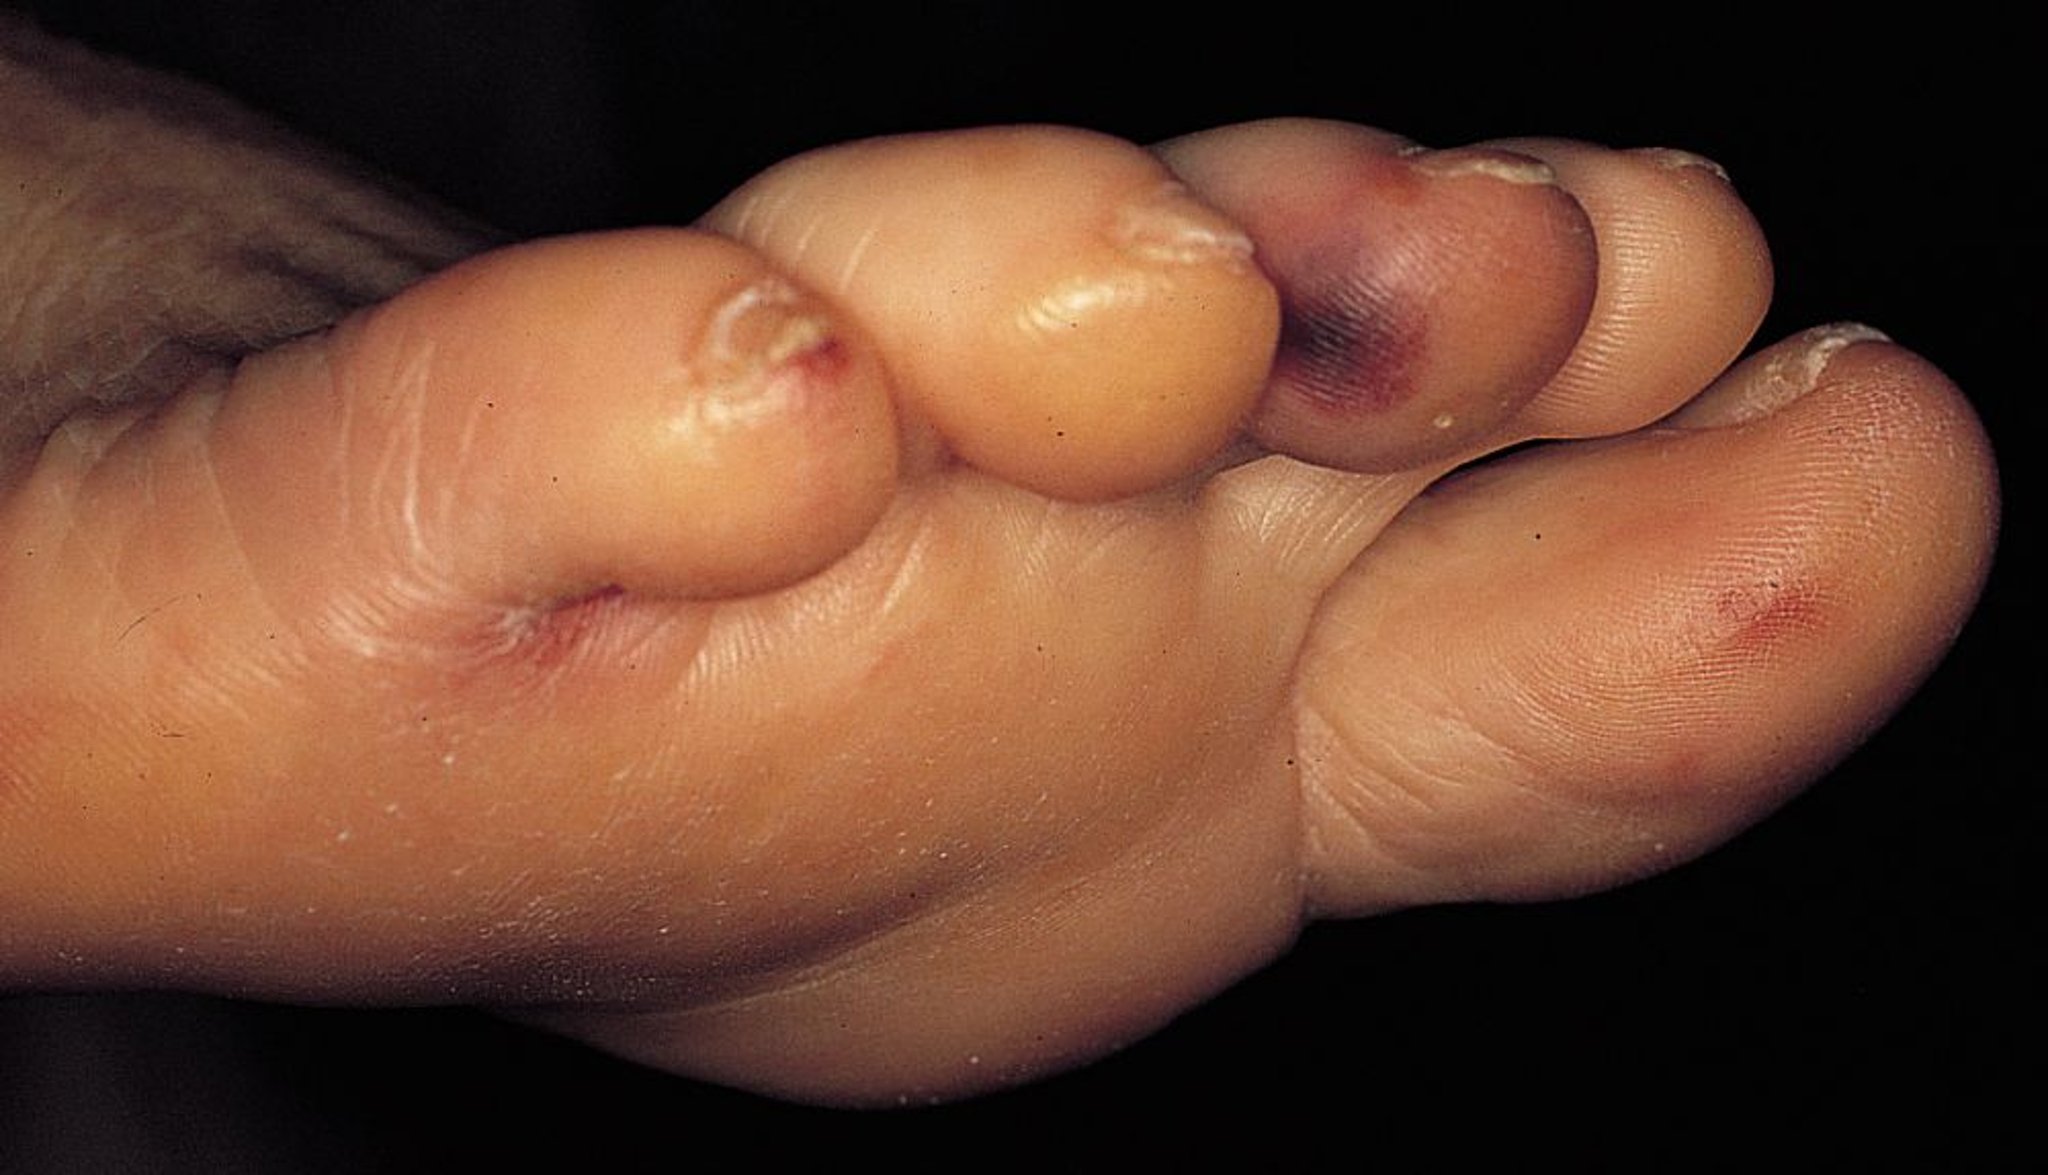

Endocardite infecciosa (nódulos de Osler)

Esse paciente com endocardite infecciosa tem múltiplos nódulos de Osler (nódulos eritematosos e sensíveis nos dedos dos pés).